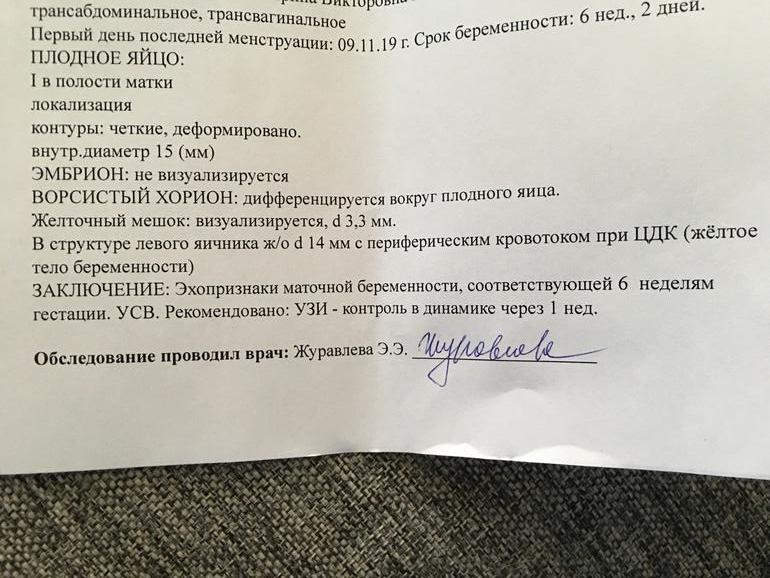

Развитие эмбриона на 8 неделе беременности